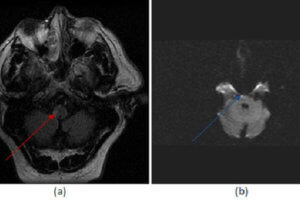

Wallenberg (lateral medullary) Syndrome

The lateral medullary or Wallenberg syndrome results from an infarct of the lateral medulla from disease in the posterior inferior cerebellar artery (PICA) or its branches. The PICA is the first major... Read more »